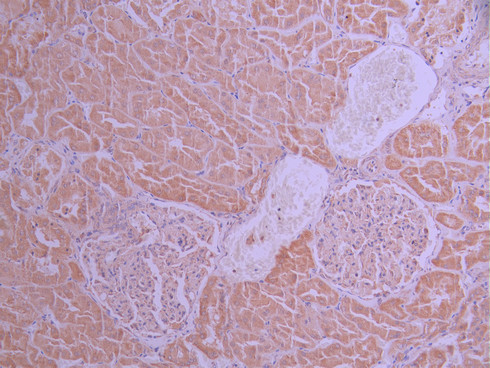

IHC image of CSB-RA108916A0HU diluted at 1:100 and staining in paraffin-embedded human kidney tissue performed on a Leica BondTM system. After dewaxing and hydration, antigen retrieval was mediated by high pressure in a citrate buffer (pH 6.0). Section was blocked with 10% normal goat serum 30min at RT. Then primary antibody (1% BSA) was incubated at 4°C overnight. The primary is detected by a Goat anti-rabbit polymer IgG labeled by HRP and visualized using 0.05% DAB.